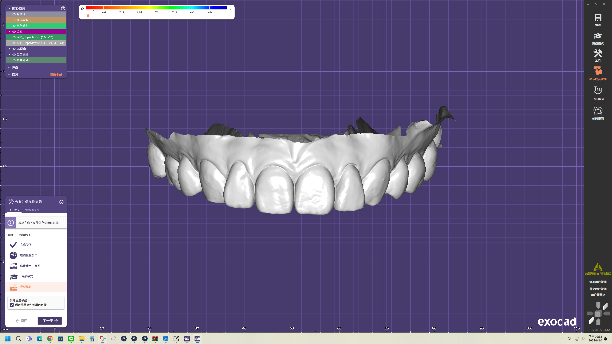

全瓷貼片是以高級陶瓷原料製成的薄透牙貼,和全瓷冠具有相同的優點;製程數位化,從口腔掃描、3D建模到齒型排列都有精確的模擬與設計,並參考大量數據以做出最符合病患需求的貼片。